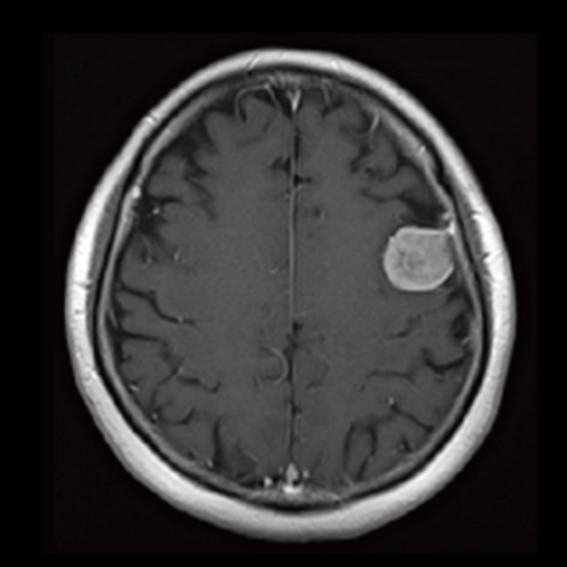

運用高科技尖端影像設備,提供貴賓精準的檢查、判讀、即時醫療、後續追蹤、健康管理或醫學中心轉介服務;從健檢診斷到後端治療,一條龍式服務。永越自成立以來,已服務超過16萬人次,每年通報件數超過千件,揪出包括:甲狀腺癌、肝腫瘤、肺癌、乳癌、子宮頸癌等重大異常的健康警訊,把握住早發現早治療的黃金關鍵。